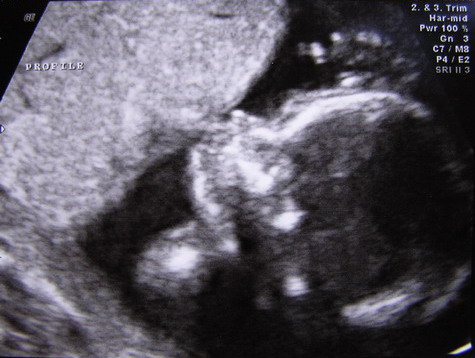

Na es a kepek: a kukis es egy profil ahol eppen a mehlepenyt szopogatta...